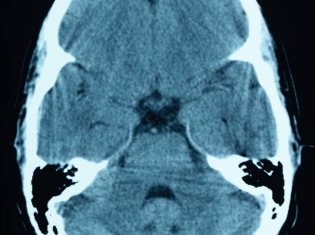

Research leader Philip LoGrasso said the study provides the first compelling data on an oral, brain-penetrating inhibitor to demonstrate this effectiveness in Parkinson's disease, a progressive, neurodegenerative disease that causes tremor and coordination problems from the loss of a group of neurons in part of the midbrain involved in motor control.